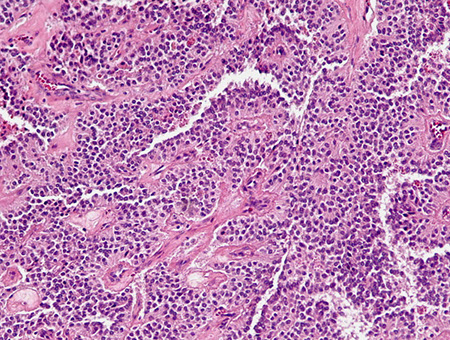

Micro: small nests or trabeculae of cuboidal cells c central nuclei, stippled chromatin, and granular cytoplasm, growing as trabecular, solid, glandular, gyriform (ribbons and festoons) or nondescript forms (and are histologically classified as such)

- highly vascular stroma

- salt n peppa chromatin

IHC: (+) CEA / CEACAM1, individual islet markers (glucagon, insulin...), NSE, chromogranin A / B, synaptophysin, opioid peptides, PR, PAX-8, CD56